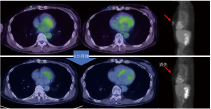

当院のBNCT症例

写真内の電子捕獲は一貫しています。CT では捉えられない播種の例が再発病変の周囲で見つかりました。 この種の再発病変は通常乳がんですが、病変の範囲を特定するのは容易ではなく、放射線治療、陽子線、重粒子線は適していません。

BNCT は巨大な腫瘍を治療できます。ただし、他の放射線療法と同様、画像検査で腫瘍が縮小し始めるのは治療後 2 か月目以降です。